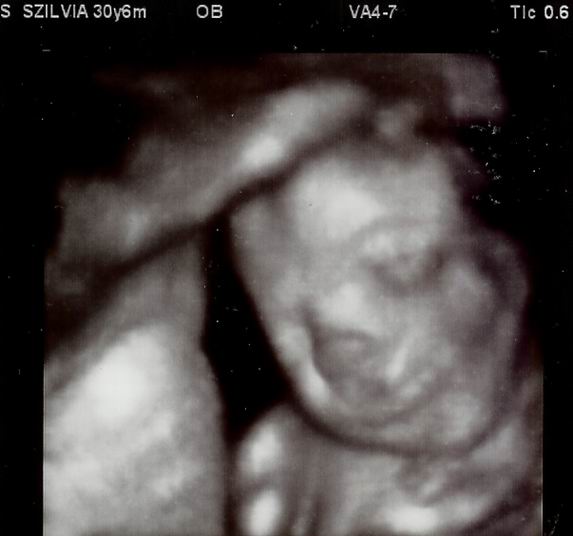

Pusz: Melinda (32+5)